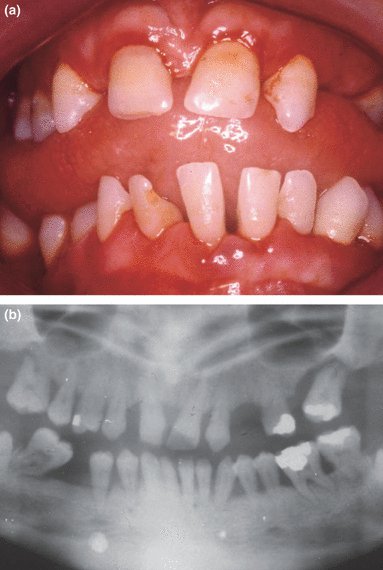

Пациенты, которые курят, имеют значительно более низкий шанс успешного лечения пародонтита. Даже после проведения профессиональной чистки зубов, кюретажа и других процедур, процесс заживления у курильщиков протекает намного медленнее, а риск рецидива заболевания значительно выше.

Например, после операции по регенерации тканей пародонта, у курильщиков часто наблюдается меньший объем новообразованной кости и связки, чем у некурящих. Это связано с тем, что курение препятствует образованию новых сосудов, необходимых для доставки питательных веществ и кислорода к местам повреждения.